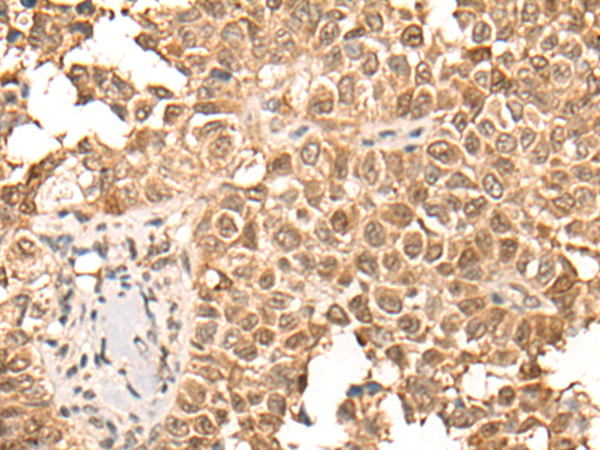

ELISA, IHC |

IHC positive control: |

Human ovarian cancer and human thyroid cancer |

IHC Recommend dilution: |

25-100 |